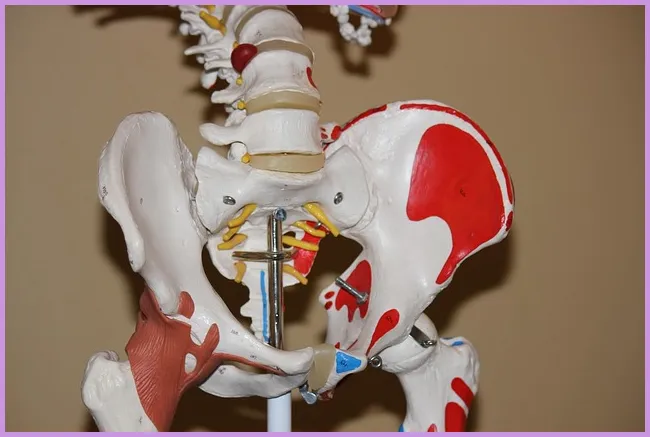

류마티스 관절염은 면역 시스템이 자신의 관절을 공격하여 염증을 발생시키는 자가면역 질환입니다. 이는 지속적인 통증과 불편함을 유발하며, 관절의 기능을 저하시킬 수 있습니다. 초기 단계에서는 일반적인 증상으로 시작하여 시간이 지남에 따라 악화될 수 있습니다. 이 질환은 주로 손, 발, 무릎과 같은 관절에 영향을 미치는 경향이 있습니다. 그렇다면 이 질환의 초기 증상은 무엇일까요?

관절염의 초기 증상 중에서도 가장 눈에 띄는 것은 관절의 통증입니다. 이 통증은 아침에 더욱 심해지는 경향이 있으며, 예를 들어 아침에 일어나서 발가락의 통증으로 인해 걷기가 힘들어질 수 있습니다. 이러한 증상은 해당 관절의 염증에 의해 발생합니다. 초기 증상이 나타났다면 전문가와의 상담을 통해 조기에 대처하는 것이 매우 중요합니다.